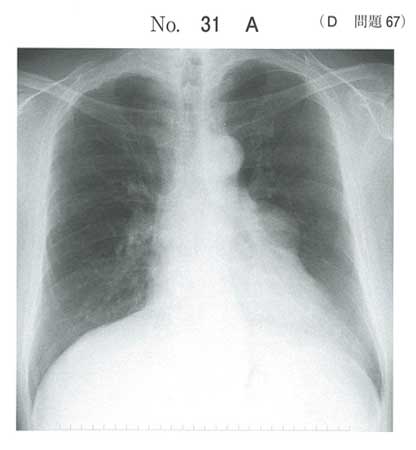

| タイトル:113D-67 | コメント数:5 | チョイ割 |

重症筋無力症+胸腺腫。確か過去の国試で赤芽球癆の合併は出ていたような…

低ガンマグロブリン血症を伴う胸腺腫→Good 症候群だったと思います